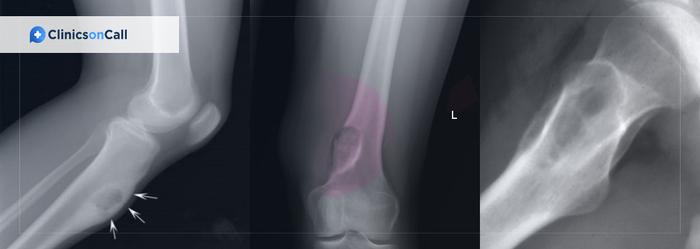

Данная костная опухоль возникает в молодом возрасте (в среднем в 20 лет) у мужчин и женщин в соотношении 2:1. Клинически заболевание характеризуется наличием выраженных болей, длящихся от нескольких недель до года или больше. Рентгенологически опухоль может начать проявляться как рентгенопрозрачная зона со слабо или хорошо очерченными краями и разной степенью минерализации. Хотя использование рентгенологического исследования очень важно, окончательный диагноз ставится только после гистопатологического заключения.

На ортопантомограмме определяется обширная рентгенопрозрачная зона, затрагивающая второй нижний моляр с правой стороны. Образование содержит кальцифицированные массы, приближающиеся к дистальному корню второго моляра, а так же несколько рентгеноконтрастных участков, расположенных на фоне зоны просветления. Данное образование являлось хорошо очерченным и вызывало выбухание и истончение костной ткани нижнего края нижней челюсти. (Фото 1).

Фото 1: Ортопантомограмма. Образование с одной полостью, имеющее рентгенопрозрачный характер, затрагивает второй нижний моляр справа и содержит участки минерализации.

Дифференциальный диагноз проводился с цементобластомой, остеоидной остеомой, оссифицирующей фибромой и фокальной цементно-костной дисплазией.